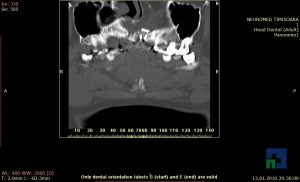

- Diagnosticul fracturilor:

- Unice

- Multiple

- Cu înfundare

- Complexe cranio-sinusale

- Complexe cranio-etmoidale

- Complexe cranio-orbitare

- Complexe cranio-faciale